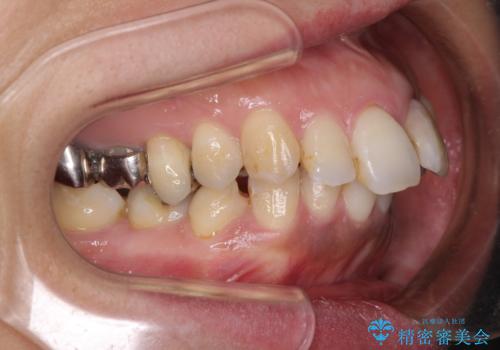

- 歯列全体が内側に倒れ込んでいることと、口元の突出感を気にして来院された患者様です。

上下ともに歯列が狭窄しており、前方に突出している状態でした。

歯が重なるような叢生も認められたため、上下左右の第一小臼歯4本を抜歯して、口元が引っ込むように治療を行うこととしました。